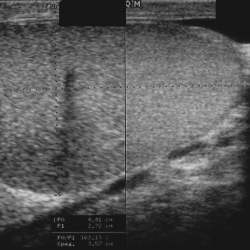

Мужчина, 60 лет. Около 3 месяцев назад появился дискомфорт в области мошонки, увеличение правого яичка.УЗИ: левое и правое МРТ: Постконтрастные: